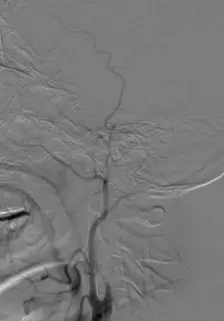

颈内动脉DSA提示颅内存在三处病变血管:大脑中动脉上干闭塞,下干的起始段局部有血栓形成以及一支M2段分支闭塞。

下干取栓后DSA可见下干开通,M2分支以及大脑中动脉上干部分开通。

使用4-20 Solitaire 支架进行MCA上干取栓。 取栓后DSA提示上干完全再通,M2远端分支仍闭塞。

使用4-20 Solitaire 支架进行M2远端分支取栓。 取栓后DSA提示三支病变血管均完全开通。